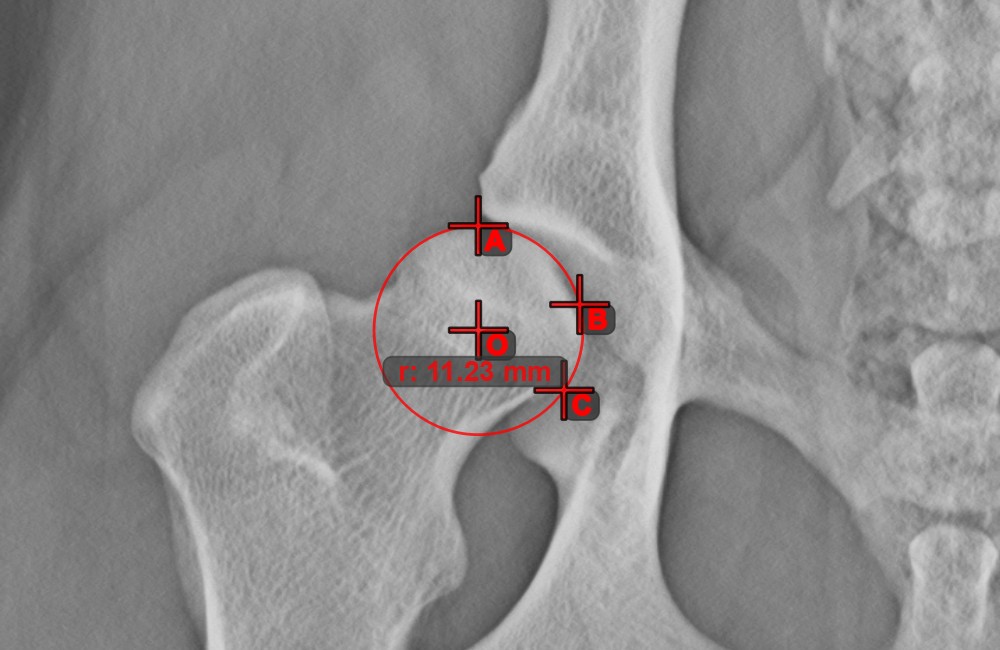

Circle from 3 Points

The Circle from 3 Points tool is a simple and effective way to create a circle from just three points.

Start by selecting the tool from the left toolbar and assign it to one of the available mouse buttons. Place the three points of the circle, or select the points from ones available on the scene. The circle will be automatically created based on the position of the three points. The origo of the circle will always be marked with O. The radius of the circle is automatically calculated.

Modify the position of the three points to change the radius of the circle by using the Select/Move Item tool.

../_images/image108.jpg